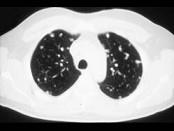

问题 女,72岁,咳嗽,胸闷,呼吸困难1月余,1年前行结肠癌根治术,CT检查如图,请选择最可能的诊断 ( )

选项 A.肺癌 B.肺转移瘤 C.尘肺 D.间质性肺炎 E.粟粒型肺结核

答案 B